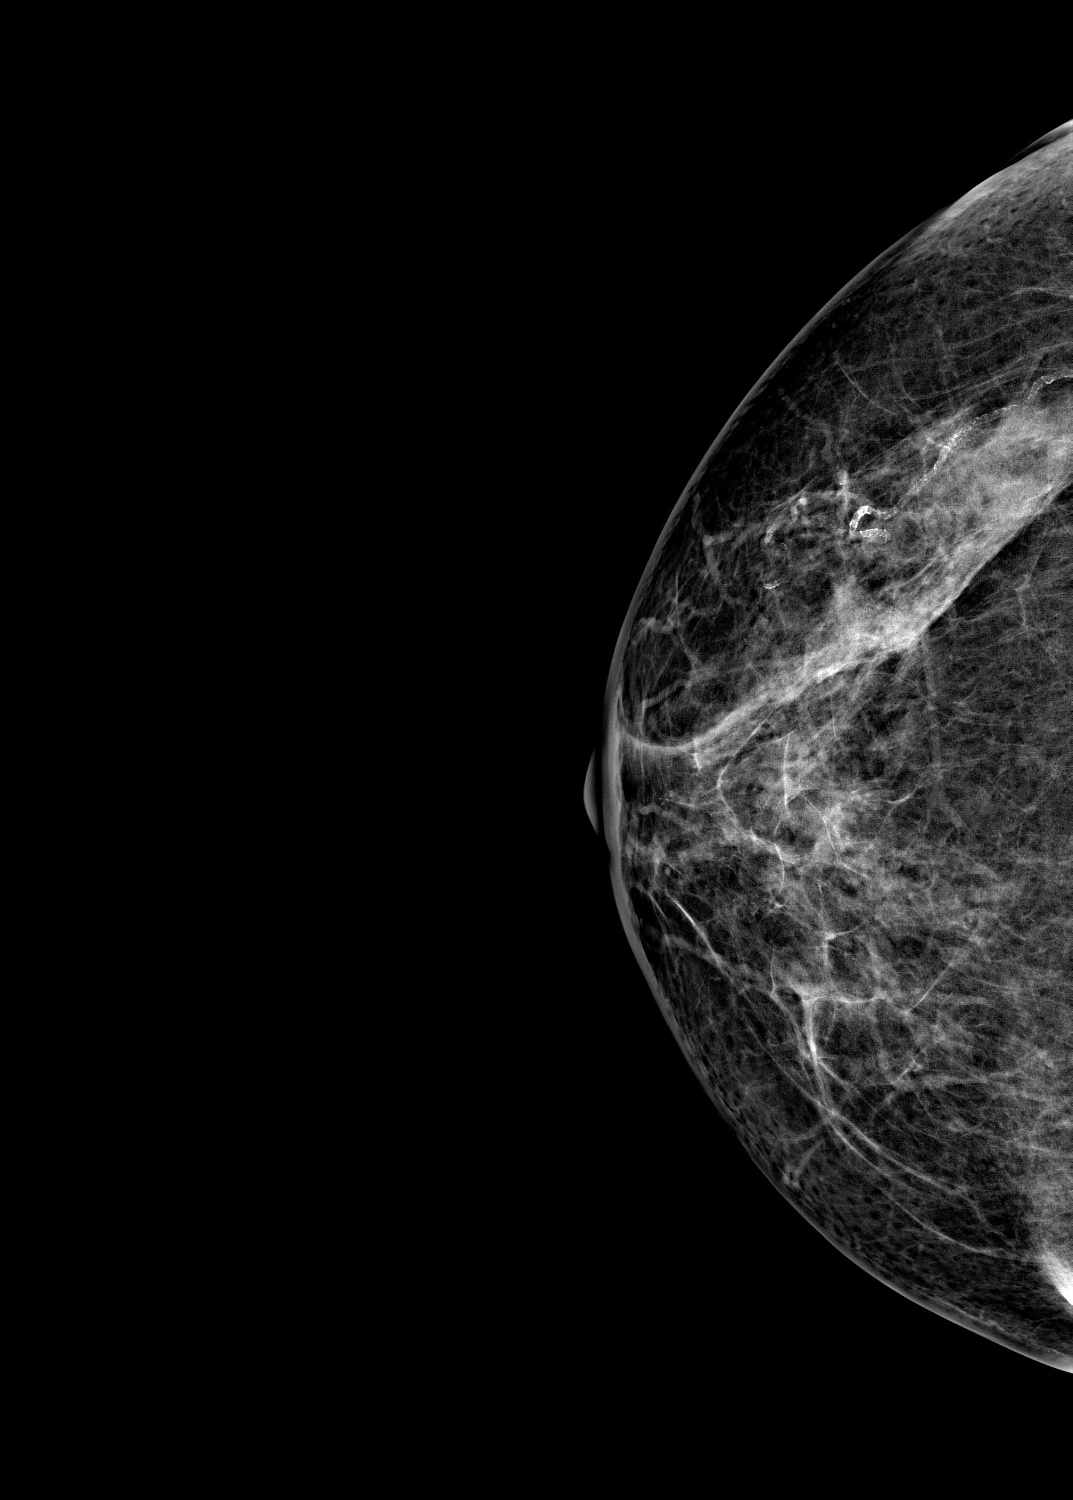

Маммограф выявляет опухоли молочной железы размером от 1-2 мм, которые не определяются при осмотре врача и самообследовании. На снимках хорошо различимы мельчайшие скопления солей кальция (от 87 мкм), тяжистые и другие перестройки тканей, характерные для рака груди 1-2 стадии. Высокую информативность, диагностическую ценность изображений обеспечивает цифровой детектор с самым чувствительным в мире сцинтиллятором. На снимках также определяются воспалительные процессы, кисты и даже небольшие повреждения.

Универсальный размер детектора делает обследование женщин с большим размером груди проще и безопаснее. Функция съемки молочных желез с имплантами позволяет обследовать эту категорию пациенток. На снимках хорошо различимы и ткани груди, и грудные эндопротезы.

Рентгеновский маммограф BRESTIGE EXPERT INDIRECT оснащен чувствительным сенсором непрямого преобразования на основе аморфного кремния. Цифровой детектор этого типа отличается надежностью и обеспечивает высокое качество изображения. Детальная «картинка» получается благодаря активной матрице, содержащей 2816 × 3584 пикселей, и хорошей квантовой эффективности (до 50%). На снимках ясно различимы даже небольшие изменения в структуре тканей и малоконтрастные образования.

Полноформатный детектор облегчает и ускоряет обследование женщин с большими молочными железами, а также делает его безопаснее. Пациенткам с грудью до пятого размера включительно для полноценного исследования достаточно 4 снимков: по 2 для каждой молочной железы. Аппараты, укомплектованные детектором меньшего размера, требуют 8 экспозиций.

Режим позволяет проводить маммографию у пациенток с грудными эндопротезами. На снимках хорошо видны ткани груди. Снимки отражают состояние импланта, в том числе его серьезные повреждения.